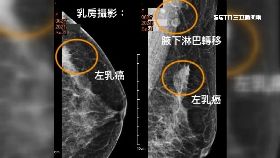

拖2年才就醫 婦人把乳癌腫瘤養到5公分大

一名50歲婦人,二年前摸到乳房硬塊但未就醫,最近她發...

28歲罹乳癌「無遺傳基因」壞習慣曝

乳癌是台灣婦女發生率最高的癌症,居女性癌症第一,死亡...